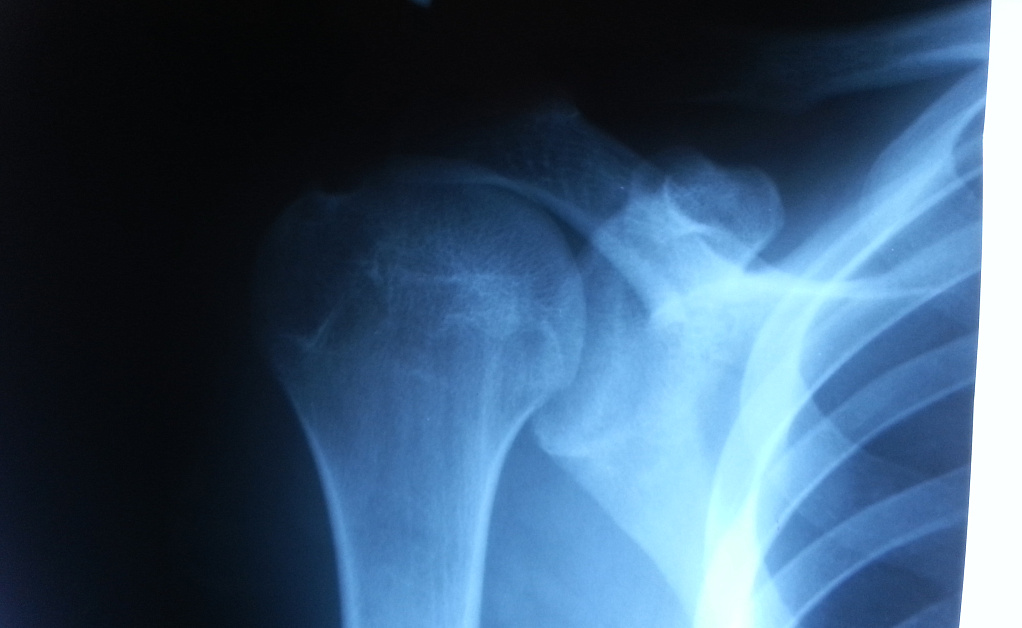

- переломы ключицы, головки плечевой кости, лопатки;

- вывихи и подвывихи плечевого сустава;

- артроз, остеоартрит и другие дегенеративные изменения;

1. Прямая проекция. Стандартный снимок, позволяющий оценить общее состояние плечевого сустава. Пациент располагается стоя или сидя, а рентгеновский луч проходит через плечо спереди назад.

2. Боковая проекция. Позволяет детально рассмотреть суставные поверхности и выявить смещения костей. Используется для диагностики вывихов и сложных переломов.

3. Косая проекция. Применяется для более точного анализа костных структур, особенно лопатки и головки плечевой кости. Позволяет оценить состояние суставной щели.

Да, на снимках будут видны сужение суставной щели, костные разрастания и другие признаки артроза.